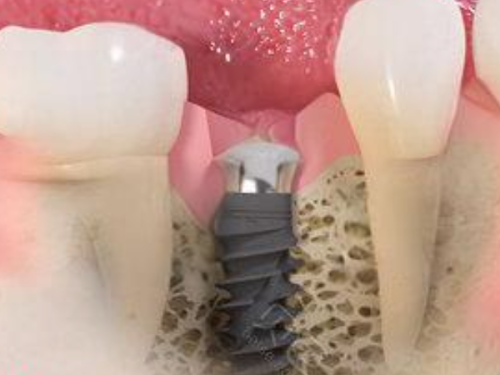

宣立国医生,从事口腔临床工作多年,在种植牙领域有着丰富的经验和深厚的技术功底。他擅长各种复杂种植牙手术,能够根据患者的具体情况制定个性化的种植方案,让患者重新拥有健康的牙齿。

种牙是一项对技术和经验要求特别高的口腔治疗项目,特别多患者都担心种牙的成效和安心性。那么,北京劲松口腔(方庄店)种牙靠谱吗?我们可以从医生和患者口碑两个方面来了解。

从医生方面来看,前面我们已经介绍了北京劲松口腔(方庄店)的医生团队,他们不仅专精技术实力强,而且临床经验多。在种牙过程中,医生会进行详细的口腔检查和评估,制定科学合理的种植方案,确保种牙的成功几率和成效。